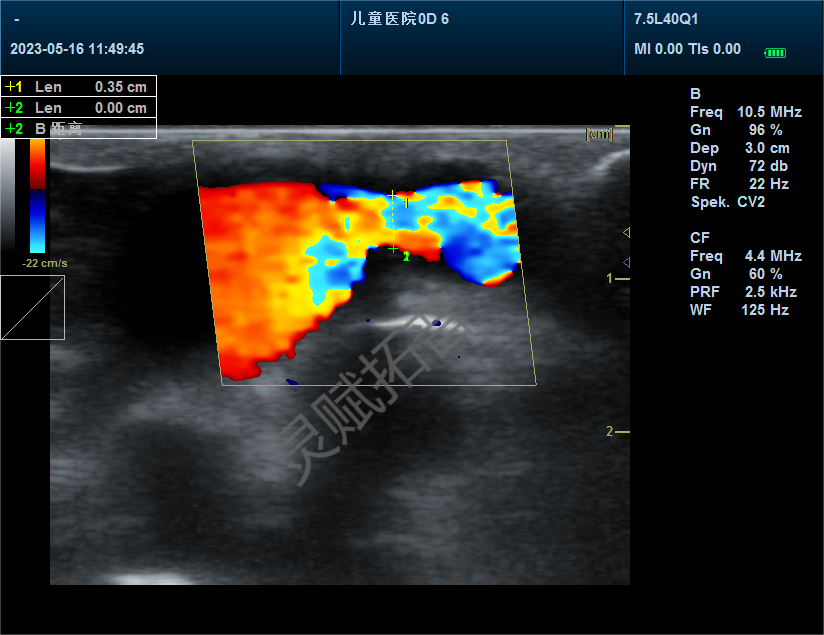

超声心动图显示室腔缩窄、心肌肥厚增大

手术后13周比格犬超声结果